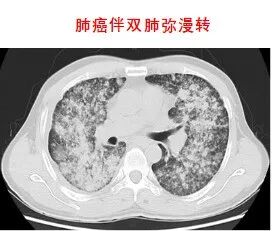

同步放化療(鼻咽癌伴頸部淋巴結轉移)